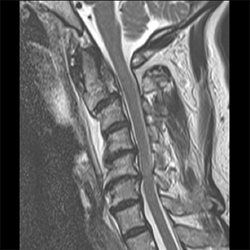

Cervical Spine Trauma Case 09